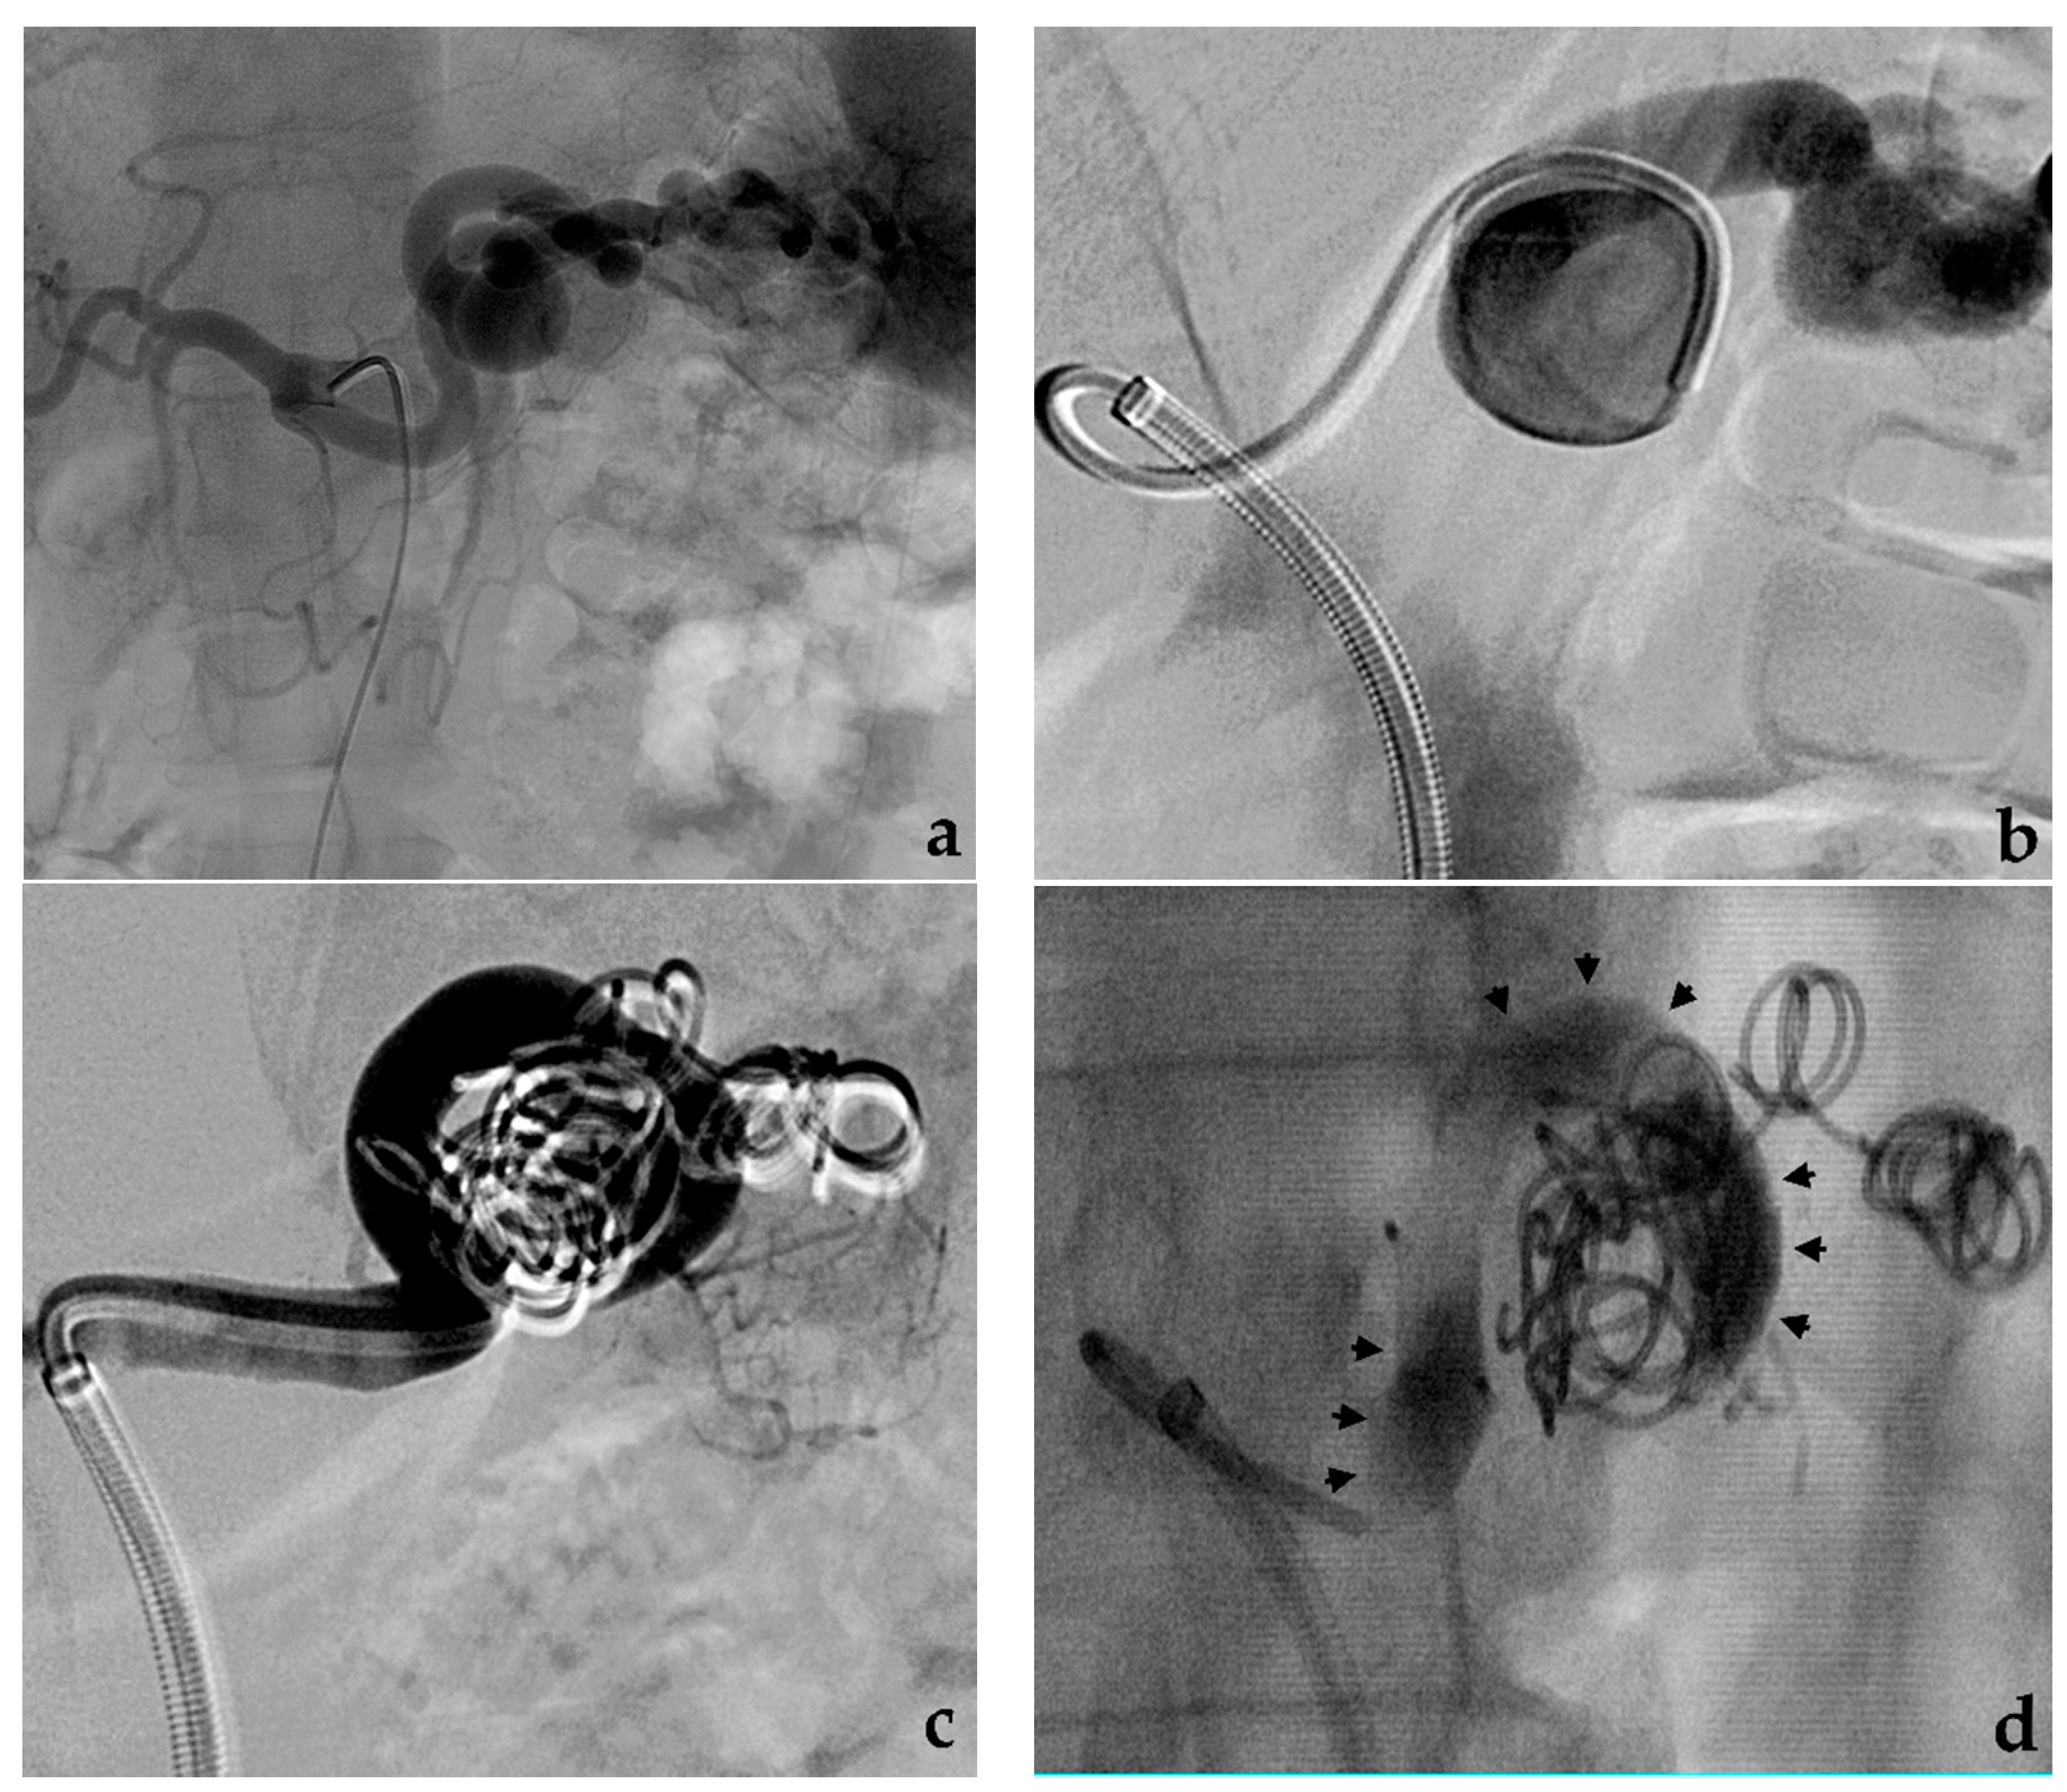

3.2. Stent-Assisted Coil Embolization

- Wei, X.; Sun, Y.; Wu, Y.; Li, Z.; Zhu, J.; Zhao, Z.; Feng, R.; Jing, Z. Management of wide-based renal artery aneurysms using non covered stent-assisted coil embolization. J. Vasc. Surg. 2017, 66, 850–857. [Google Scholar] [CrossRef]

- Secco, G.; Chevallier, O.; Falvo, N.; Guillen, K.; Comby, P.O.; Mousson, C.; Majbri, N.; Midulla, M.; Loffroy, R. Packing technique with or without remodeling for endovascular coil embolization of renal artery aneurysms: Safety, efficacy and mid-term outcomes. J. Clin. Med. 2021, 10, 326. [Google Scholar] [CrossRef]

- Ma, T.; He, Y.; Zhong, W.; Luo, G.; Li, Q.; Wang, Z.; Zhang, H.; Wu, Z.; Qiu, C. Mid-term results of coil embolization alone or stent-assisted coil embolization for renal artery aneurysms. Ann. Vasc. Surg. 2021. [Google Scholar] [CrossRef]

- Bracale, U.M.; Narese, D.; Ficarelli, I.; De Laurentis, M.; Spalla, F.; Dinoto, E.; Vitale, G.; Solari, D.; Bajardi, G.; Pecoraro, F. Stent-assisted detachable coil embolization of wide-necked renal artery aneurysms. Diagn. Interv. Radiol. 2017, 23, 77–80. [Google Scholar] [CrossRef] [PubMed]